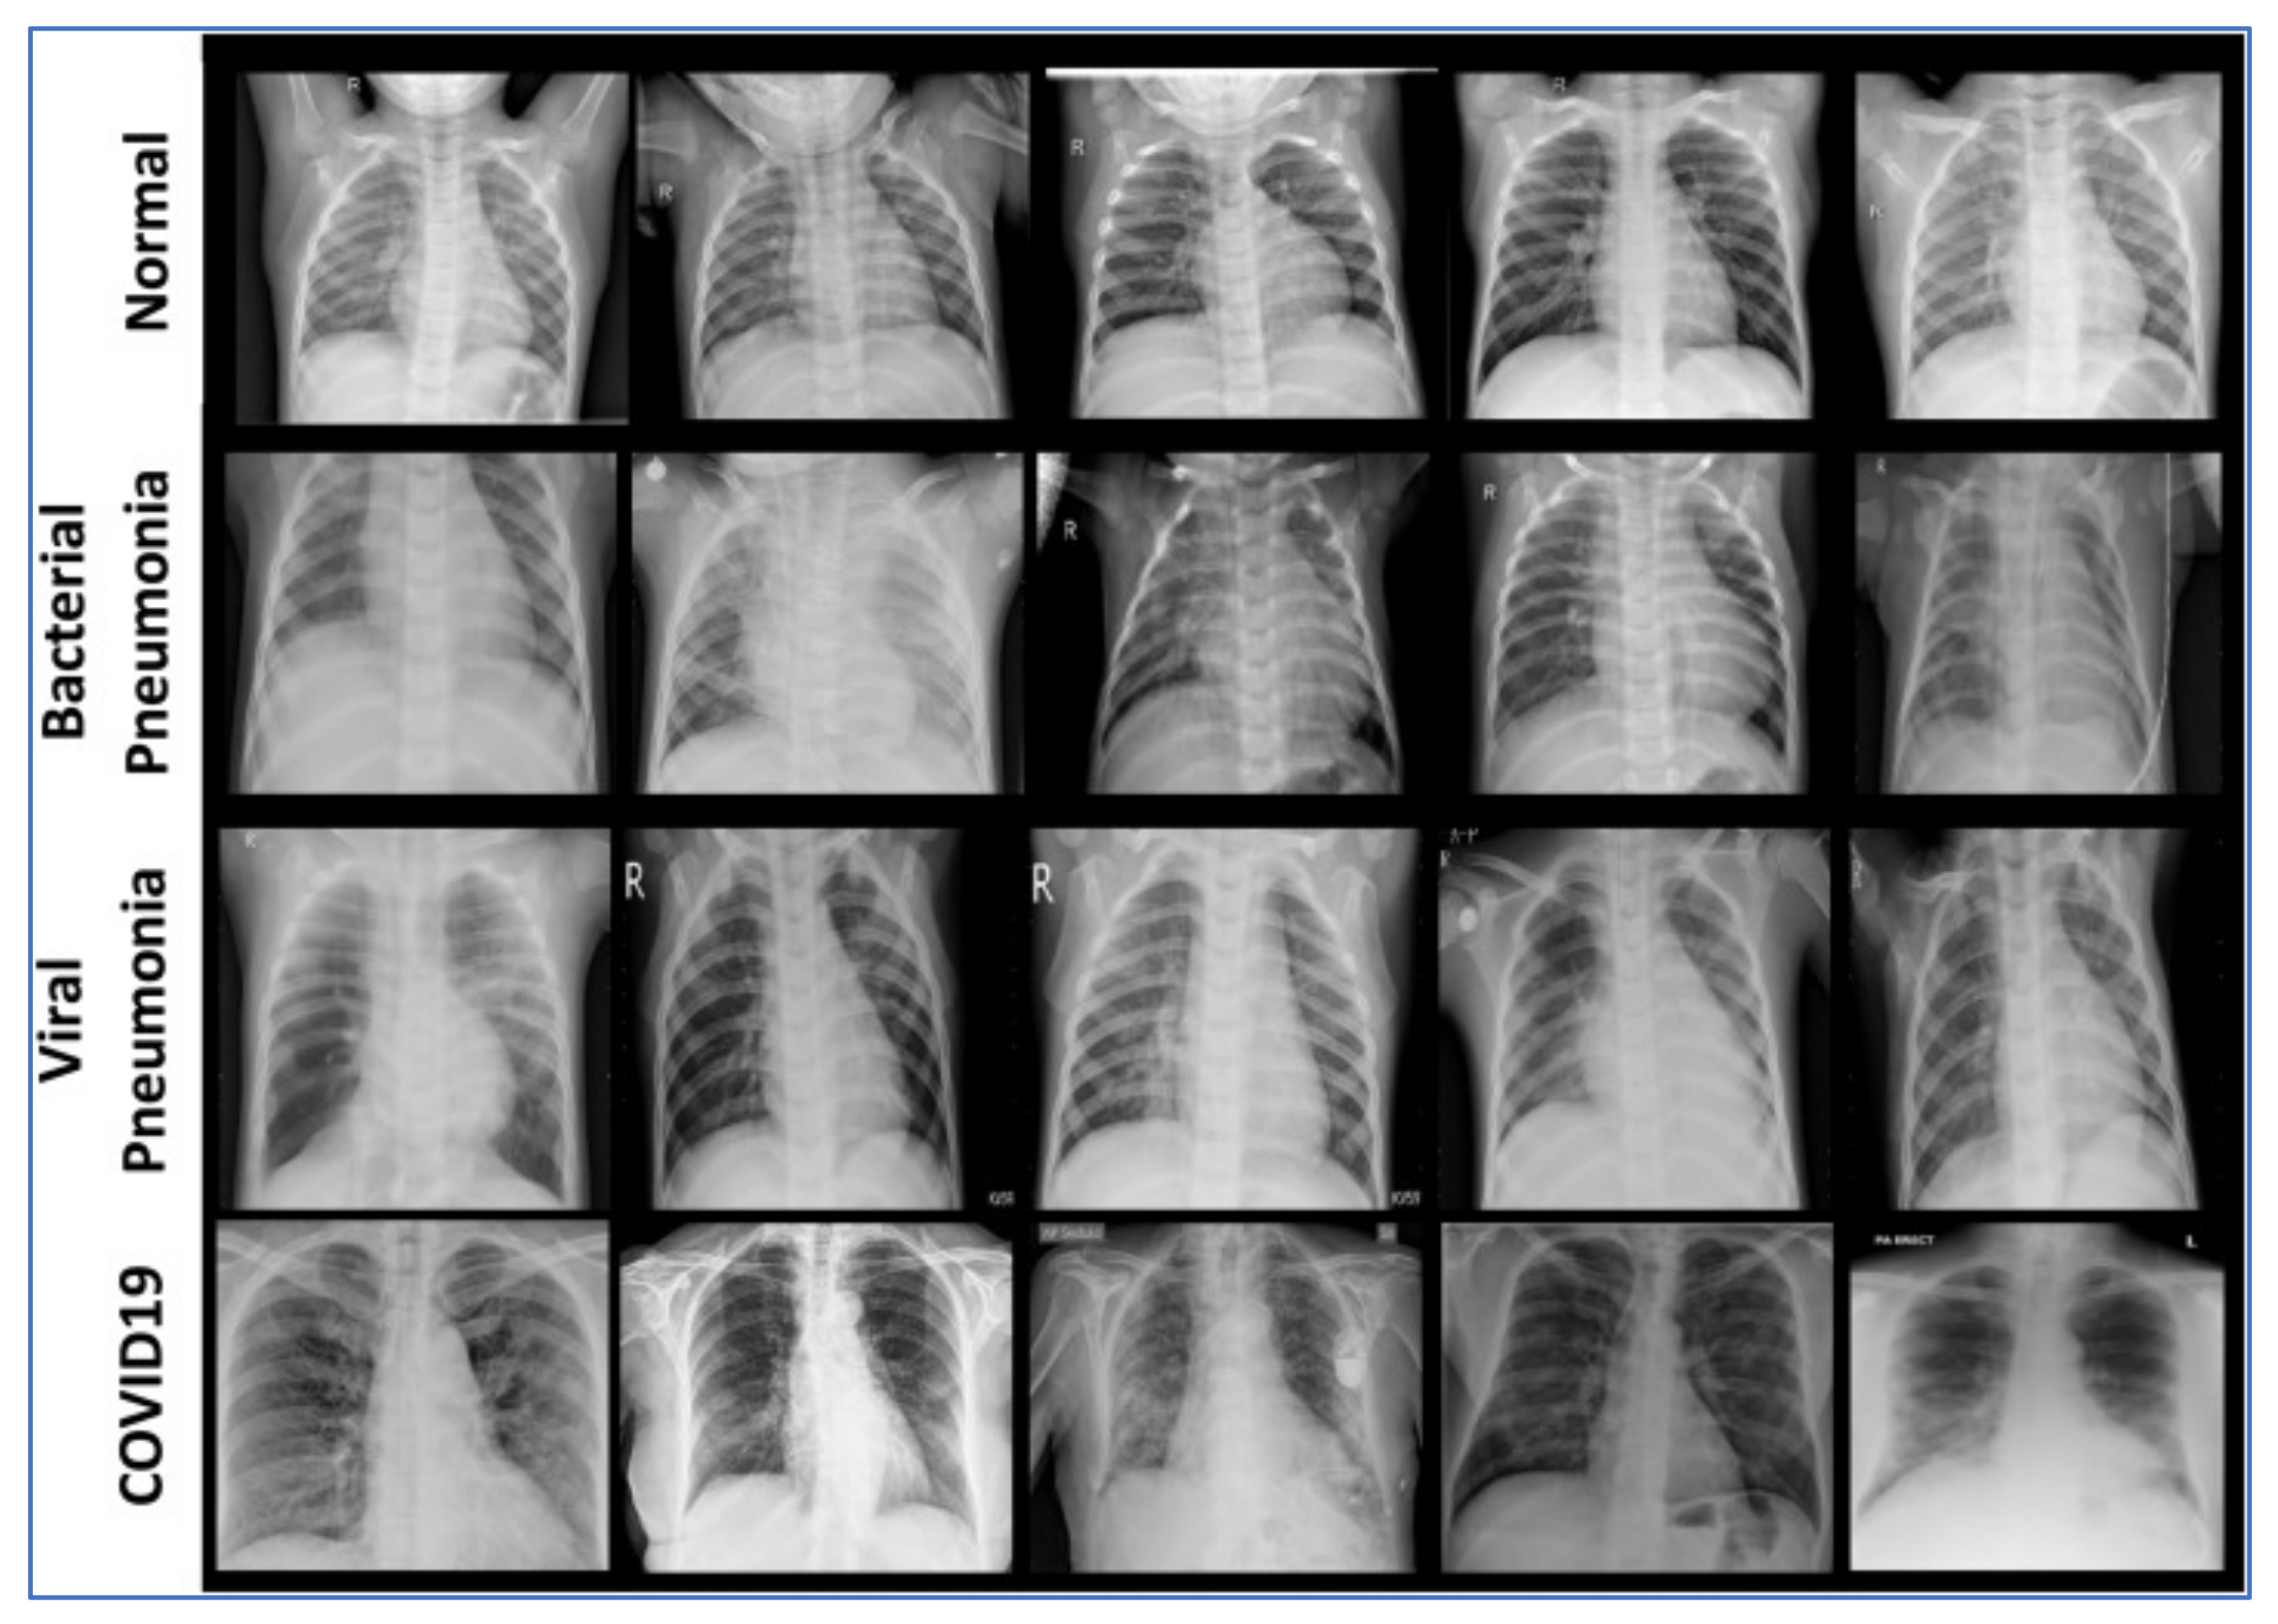

3. Proposed Method

4. Experimental Results

4.1. Feature Extraction Step

4.2. Data Sets

4.3. Results Analysis